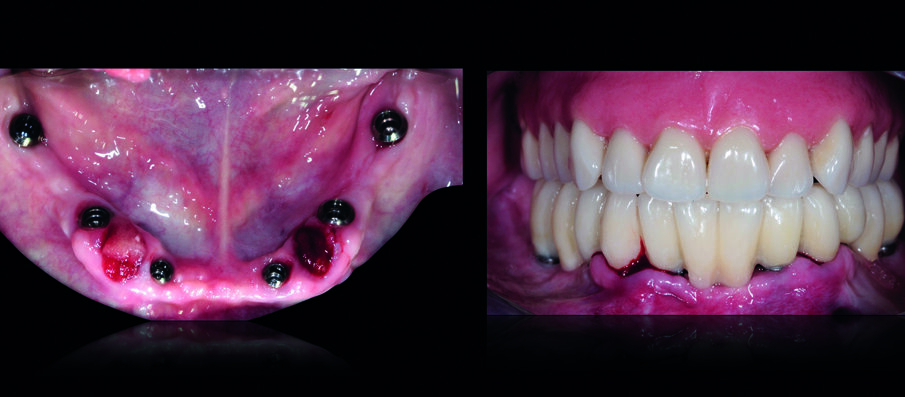

Dopo la loro osteo-integrazione, gli impianti sono stati improntati e, dopo aver registrato la posizione di relazione centrica alla dimensione verticale già testata, è stata verificata la loro posizione utilizzando una placca in resina che ha permesso anche di confermare l’adeguatezza della dimensione verticale di occlusione. Gli ultimi due denti residui sono stati estratti ed è stata consegnata alla paziente una protesi provvisoria fissa inferiore, avvitata sugli impianti (Fig. 10). Nei 30 giorni successivi sono stati valutati funzione, occlusione, fonetica ed estetica e sono state trasferite tutte le informazioni delle protesi provvisorie in quelle definitive. La protesi superiore è stata duplicata e tale replica è stata utilizzata per eseguire l’impronta di precisione del mascellare edentulo (Fig. 11).

La finalizzazione della riabilitazione ha perciò previsto due soluzioni protesiche completamente differenti tra loro: una protesi fissa inferiore avvitata su sei impianti (in metallo-ceramica) ed una protesi rimovibile superiore con denti personalizzati in ceramica presso-fusa) (Figg. 20, 21).

Tali soluzioni hanno permesso di ottenere tutti gli obiettivi prefissati con grande soddisfazione della paziente: ottima funzione in associazione ad una eccellente estetica (Figg. 22, 23).